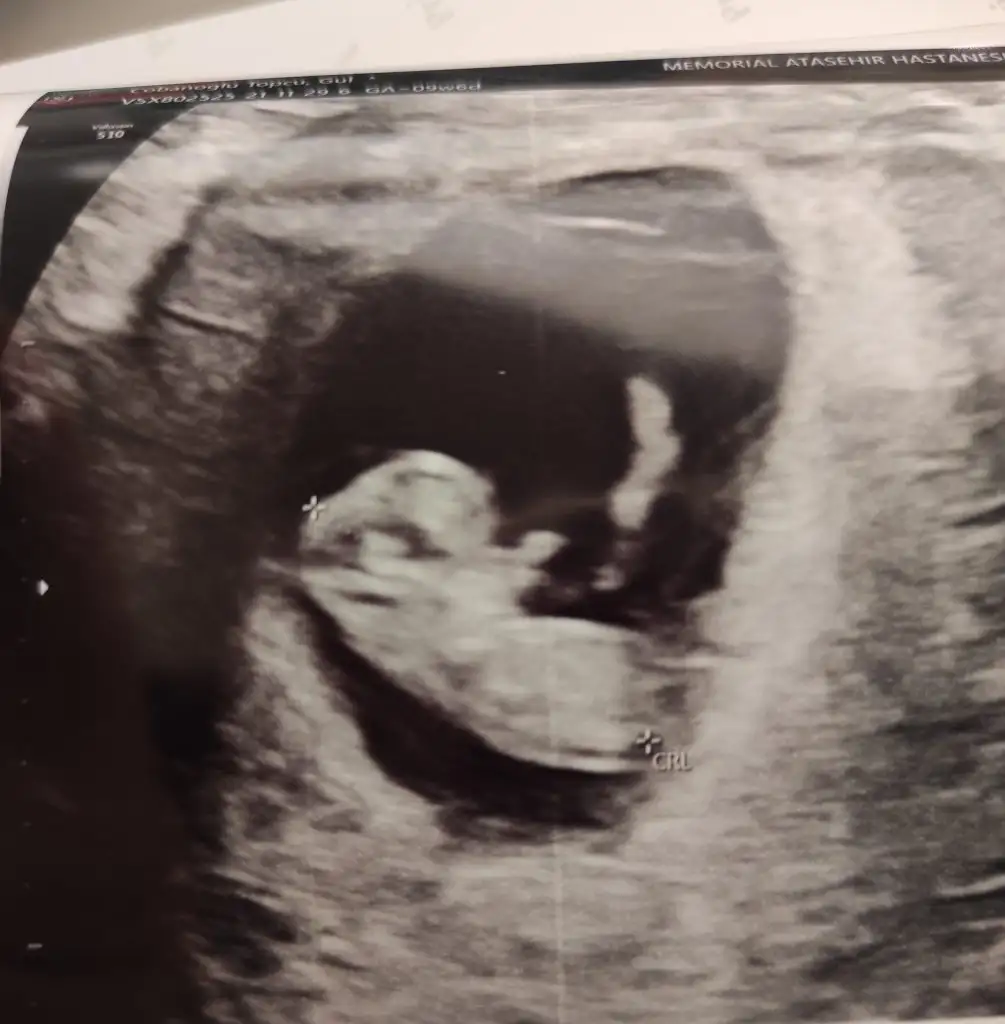

Canım 11 haftalık ultrason goruntumuz bize de bakar mısın teyzesi 😍 Ikra meyra Ikra meyra